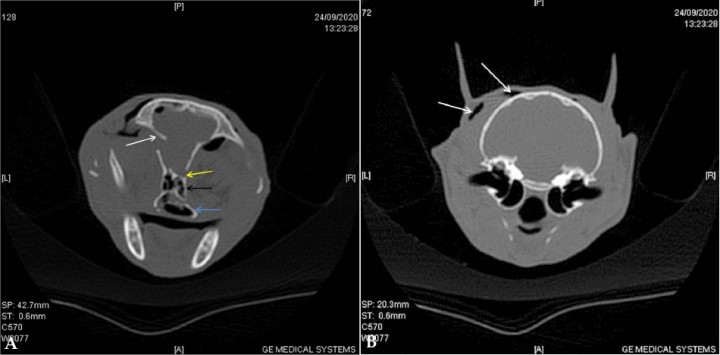

<p>Reformateo dorsal en ventana de hueso en el que se muestra que la lesión intracraneal, hipoatenuante, de márgenes bien definidos y redondeados, de densidad aire (probablemente ventrículo lateral izquierdo) (flecha sólida) comunica con el espacio extradural (flecha amarilla) mediante una fístula (flecha blanca). Además, se observa enfisema en los tejidos blandos del mismo lado (asterisco).</p>

Reformateo dorsal en ventana de hueso en el que se muestra que la lesión intracraneal, hipoatenuante, de márgenes bien definidos y redondeados, de densidad aire (probablemente ventrículo lateral izquierdo) (flecha sólida) comunica con el espacio extradural (flecha amarilla) mediante una fístula (flecha blanca). Además, se observa enfisema en los tejidos blandos del mismo lado (asterisco).

En nuestro caso, la entrada de aire hacia la cavidad craneal ocurrió a través del seno frontal y de las fracturas en dicho hueso, de la dura y de la fístula creada que actuó como válvula unidireccional (Fig. 3). Además, esta paciente presentó estornudos frecuentes debido a las lesiones en la cavidad nasal que provocaron sangrado y hematomas.

Se observaron fracturas en los huesos de las tres principales subdivisiones del cráneo: cara (maxilar, palatino), bóveda craneal (frontal y etmoides) y base de cráneo (preesfenoides). El estudio completo del TAC reveló fracturas conminutas y simples, la mayoría desplazadas y/o deprimidas (Fig. 4).